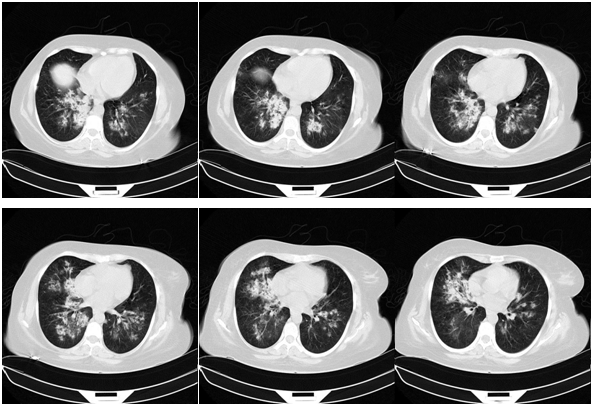

After one-month, the pulse-therapy of cyclophosphamide is repeated, in the same day, she presented by hemorrhagic cystitis (U/A: blood: +4, RBC: many, WBC: 2-3) and one-day later she complains dyspnea and hemoptesis. Also on CBC has been pancytopenic (WBC: 2300, Hb: 4.9, MCV: 94, Plt: 42000). So she’s admitted to hospital with probability relapsing and she takes the one-time pulse of Methyl-Prednisolone and plasmaphresis is done. CXR, CT-scan and bronchoscopy are repeated and bronchoscopy reveals the hemorrhagic alveolar pattern (Figure 1).

Figure 1 CXR, CT-scan and bronchoscopy are repeated and bronchoscopy reveals the hemorrhagic alveolar pattern.